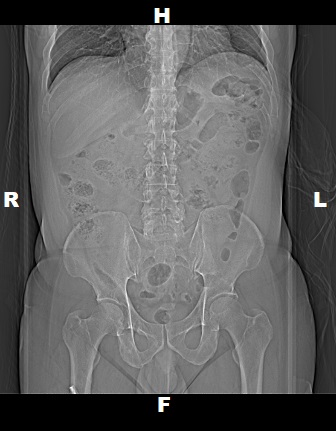

Topogram

• Position the patient in head first supine position.

• Align the patient in Mid-Sagittal plane of the table.

• Position the transverse laser light beam at the level of mid of sternum to start the topogram.

Topogram Parameters

• Topogram length: 512 mm

• Slice: 0.6 mm

• Scanning direction: Craniocoudal

• Tube position: Top

• Stop the topogram scanning when the scanning reach / pass over the inferior ischial ramus.

Non Contrast

• Plan the Scan FOV (SFOV) box at topogram image.

• Set the top line at the level of upper diaphragm.

• Set the bottom line at the level of inferior ischial ramus.

• Ensure the lateral line to cover patient’s body outline.

• Remind the patient before scanning as the breathing instruction will be given.